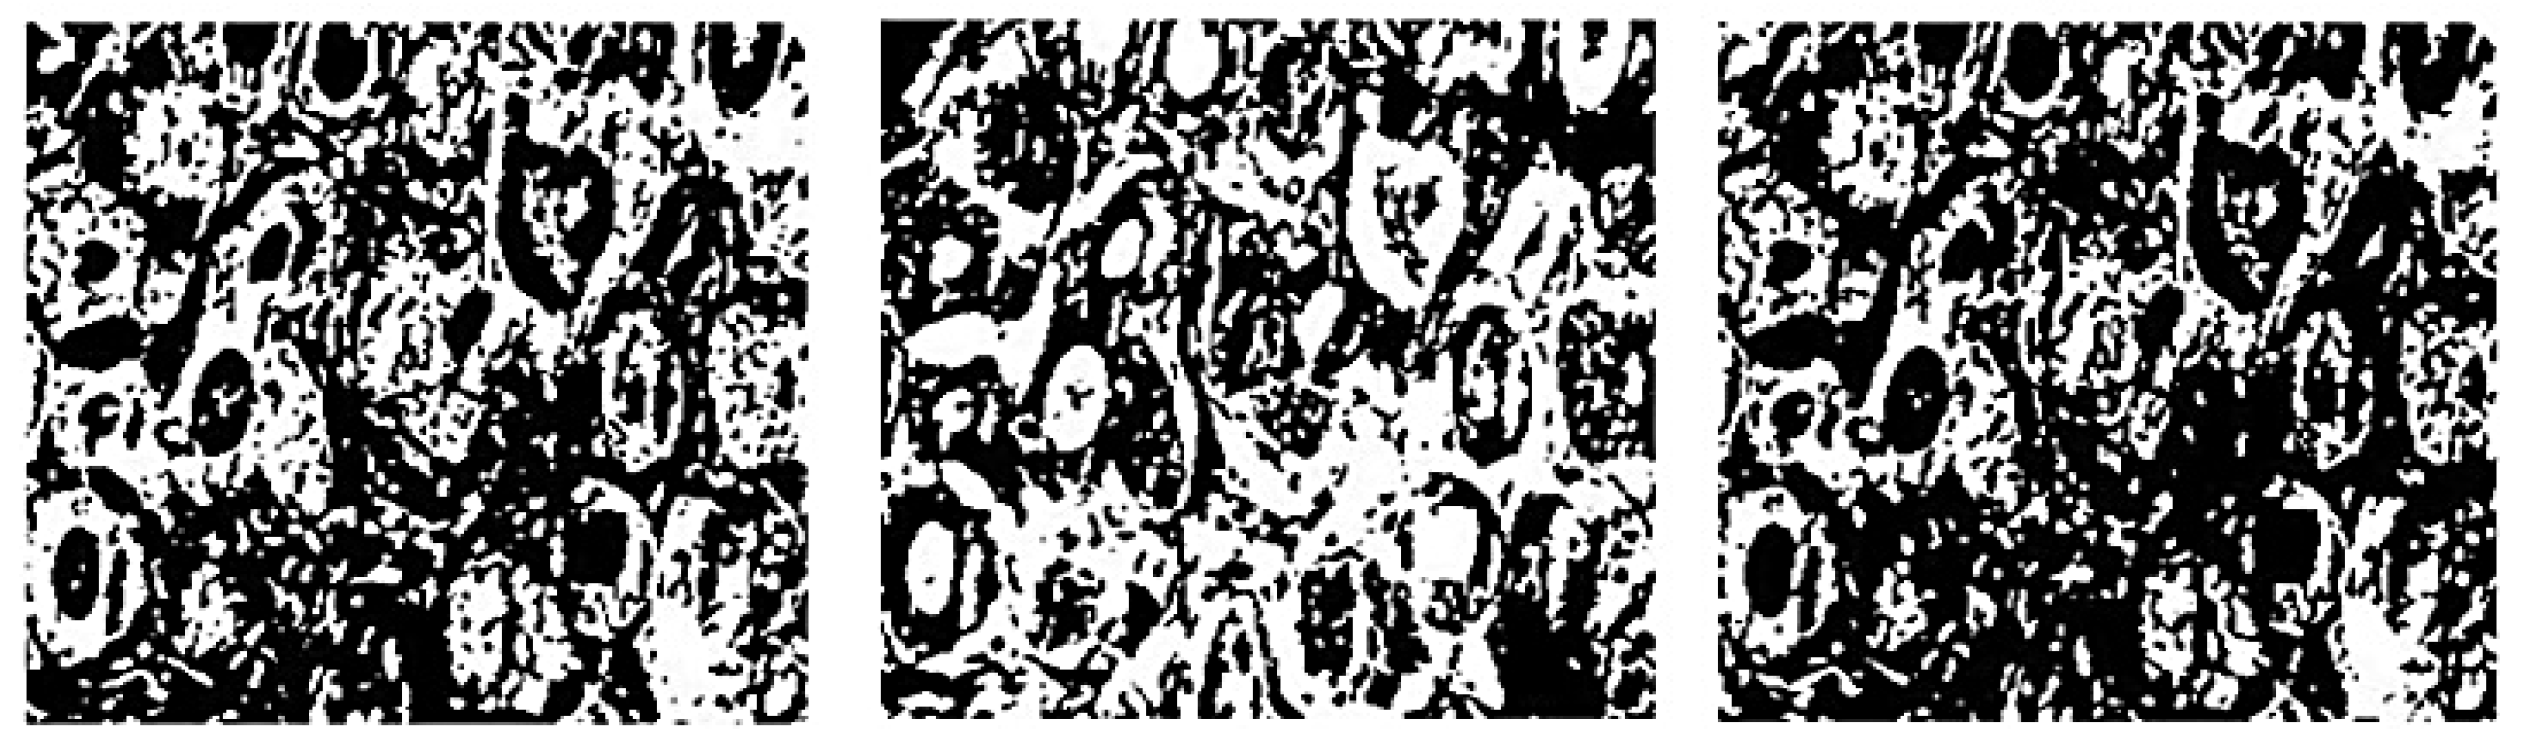

4.1. Image Processing

| 2021 | S. Alanazi et al. [90] | Kaggle 162 H&E - Invasive Ductal Carcinoma (IDC) Segmentation | Convolutional Neural Network (CNN) | Image | IDC positive and IDC negative | CNN = 87 |